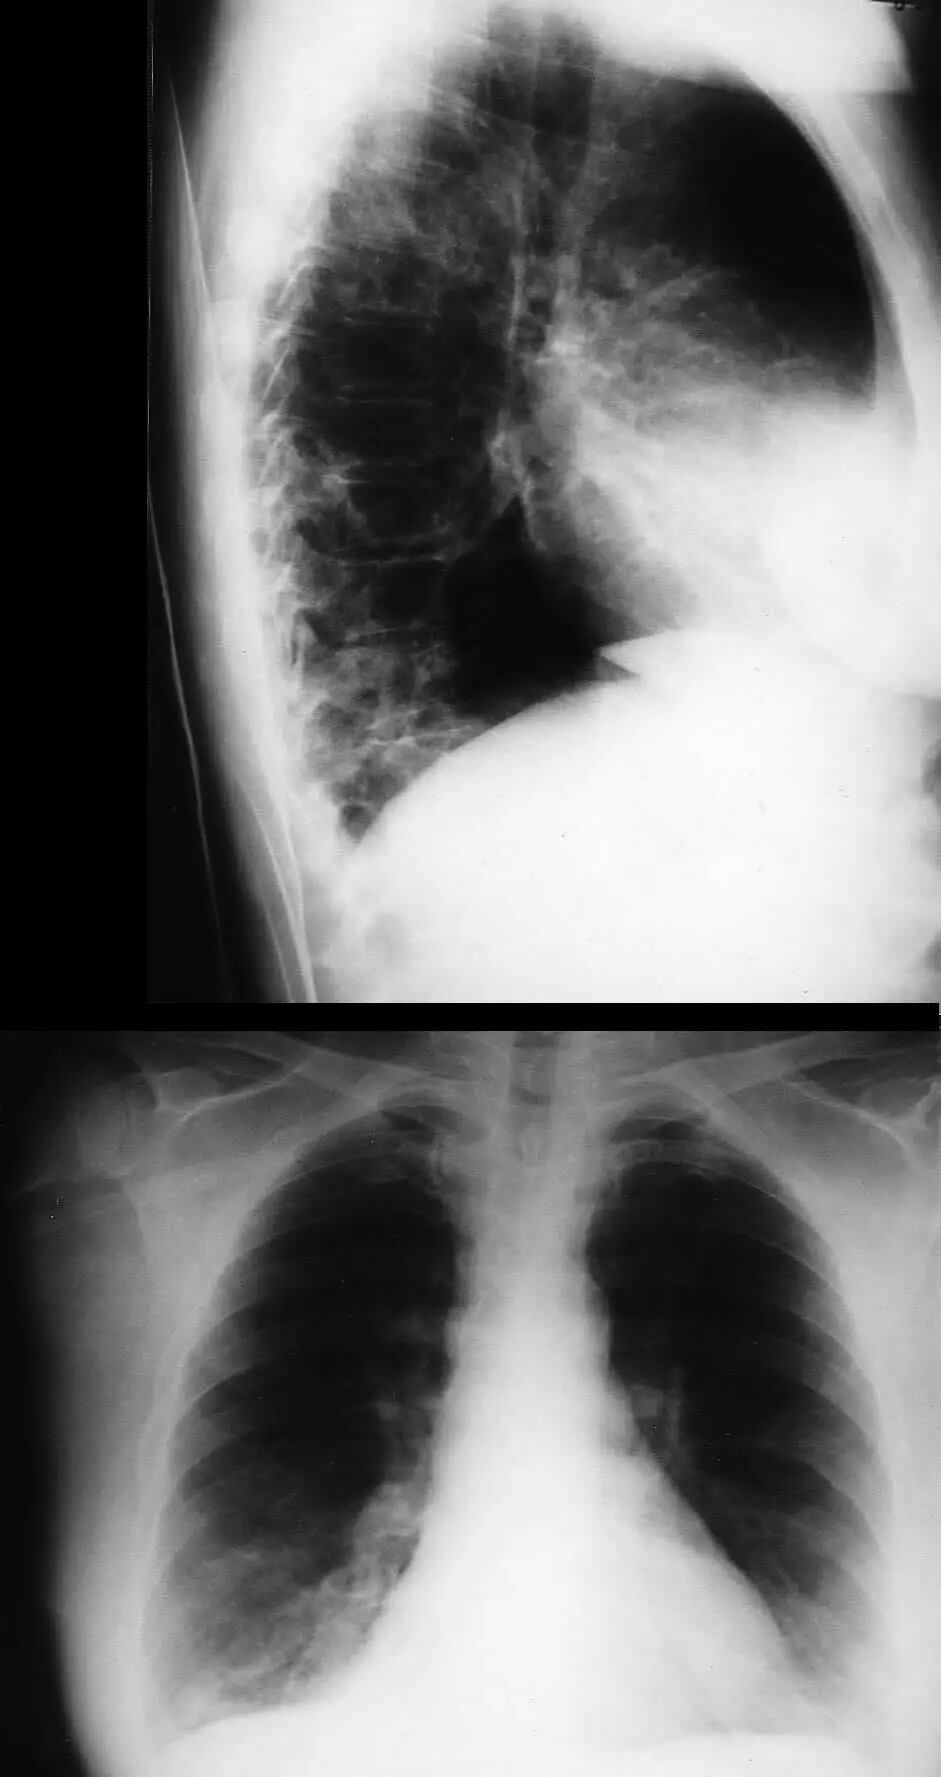

图1.1 细菌性肺炎。右上叶肺炎患者的放射影像。胸廓前后径增大,提示有慢性阻塞性肺疾病(COPD)。

图1.2 细菌性肺炎。双肺下叶肺炎患者影像。

图1.3 细菌性肺炎。早期右肺中叶肺炎的影像学表现。